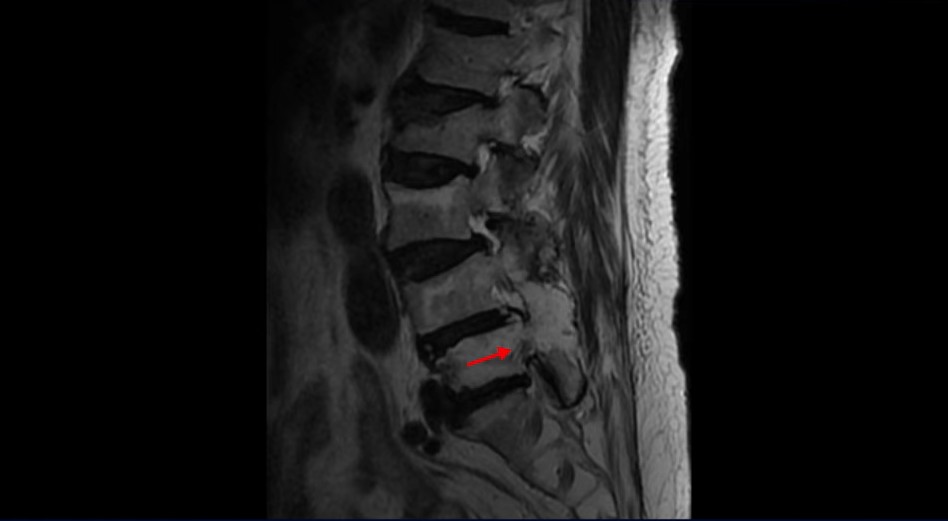

이 환자분은 협착증 수술 예약을 날짜까지 잡아놓고 넘어지면서 압박골절이 발생하고 협착증 증상 즉, 골반과 다리증상이 심하게 악화됩니다. 이분 MRI를 보시면 척추 2번 뼈에는 넘어지면서 생긴 척추압박골절이 보입니다.

4번과 5번 마디는 전방전위증이 있고 15년 전 허리수술을 받은 적이 있어서 척추 후관절과 후궁을 제거한 흔적들이 보입니다.

또 5번 1번에는 왼쪽 신경가지가 빠져나가는 추간공 즉 신경구멍이 많이 좁아져 있습니다. 이 환자분은 허리통증과 함께 왼쪽 다리 증상이 심하셨는데 이것 때문인 것으로 보입니다.